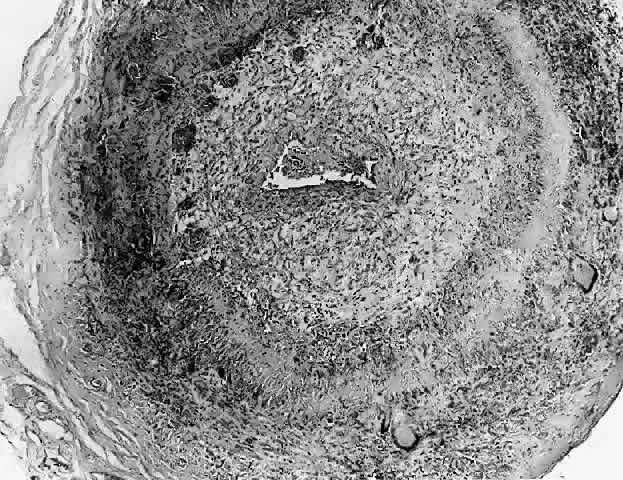

In general, idiopathic orbital inflammation is polymorphic (Figs. 5 AND 6).3,6,7,33,87,88 The cellular response seen in this disease consists of lymphocytes, plasma cells, macrophages, histiocytes, occasional neutrophils and eosinophils, epithelioid cells, and fibroblasts. These are present in varying numbers, depending on the chronicity of the inflammatory process. Intranuclear Dutcher bodies and intracytoplasmic Russell bodies may be present within many of the plasma cells since they actively participate in the inflammatory response. Children tend to have a significant number of eosinophils in their biopsy specimen. Lipogranulomatous inflammation with fat necrosis may also be present. However, the presence of noncaseating granulomas is relatively uncommon.89 This is often associated with foreign body giant cells that are responding to the release of lipid. Perivascular lymphocytic cuffing and capillary proliferation are quite common.3 Occasionally, lymphoid follicles may also be seen.

Fig. 6. Histopathologic sections demonstrating the various pathologic findings associated with idiopathic orbital inflammation. Most commonly these include lymphoid follicles, granulomas, collagen deposition, and a diffuse mixed inflammatory cell infiltrate. The normal tissue architecture is frequently disrupted by these changes. A. Many lymphoid follicles are scattered throughout orbital tissue (H&E, × 63). B. Cells of follicular center are lighter and larger than mantle of mature lymphocytes that surround the germinal zone (H&E, ×160). C. Lacrimal gland elements have undergone atrophy in advanced example of idiopathic dacryoadenitis. Fibrosis and lymphocytes have replaced a considerable amount of gland parenchyma (H&E, ×94). D. Myositis in which lymphocytes are loosely aggregated below center and infiltrate between extraocular muscle fibers (H&E, ×160). E. Cuffing of small vessels by mature lymphocytes. Note loose edematous interstitium between disrupted muscle fibers (H&E, ×240). F. Progressive fibrosis of retrobulbar fat (H&E, ×25).

With progression of the disease process there is increased fibrosis and collagen deposition, which separates the various inflammatory elements. There is also an associated thickening of the connective tissue within the extraocular muscles. With chronicity there will be actual loss of muscle tissue and its replacement with connective tissue. In the lacrimal gland there is hyperplasia of the periductal and periacinar connective tissue. As this progresses, there will be actual destruction of the lacrimal acini.76 In the sclerosing types of idiopathic orbital inflammation there is extensive fibrosis surrounding and replacing all normal orbital tissues.76,90,91 Only a minimal cellular response is present in such instances. At times this connective tissue reaction may be so dense as to have the consistency of cartilage.